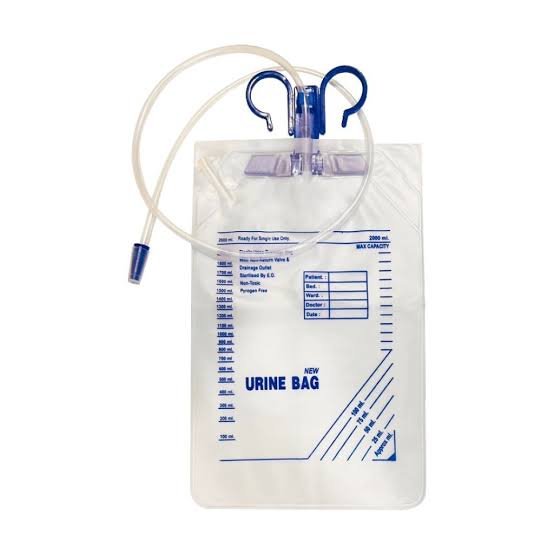

Urine Collection Bag With Top Outlet

Urine Collection Bag With Top OutletOur ProductsFrom SurgicaveUplode:9 months ago from India